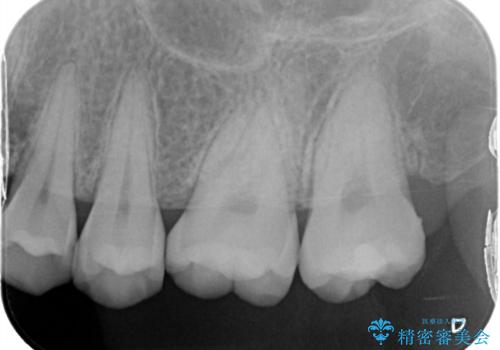

レントゲンから昔詰めた保険の詰め物が入っていることが確認できました。詰め物と歯の隙間が虫歯になっていたためしっかり取り除き、適合の良いセラミックインレーを入れました。